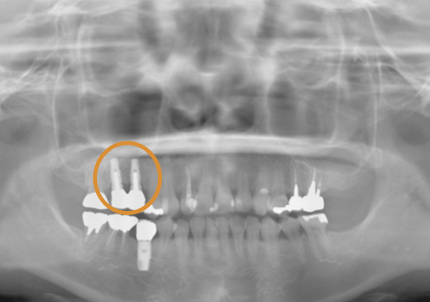

2.右側上顎洞サイナスリフト後にインプラント埋入

↑ サイナスリフト術前

↑ サイナスリフト術後

↑ 右上サイナスリフト後にインプラント埋入